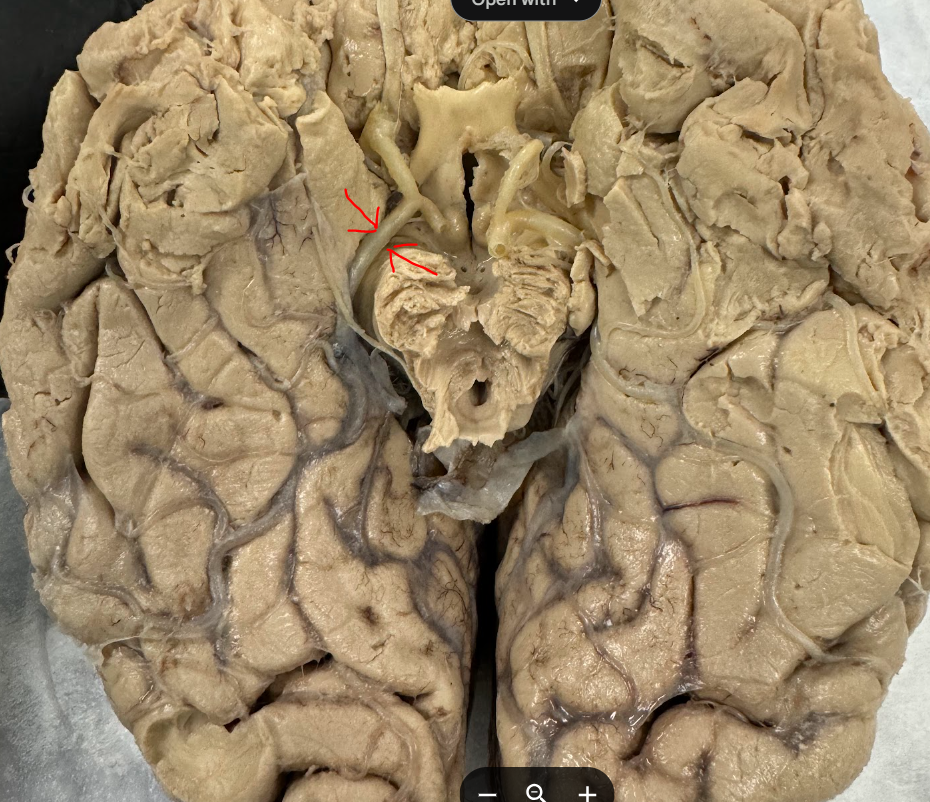

Anterior cerebral artery